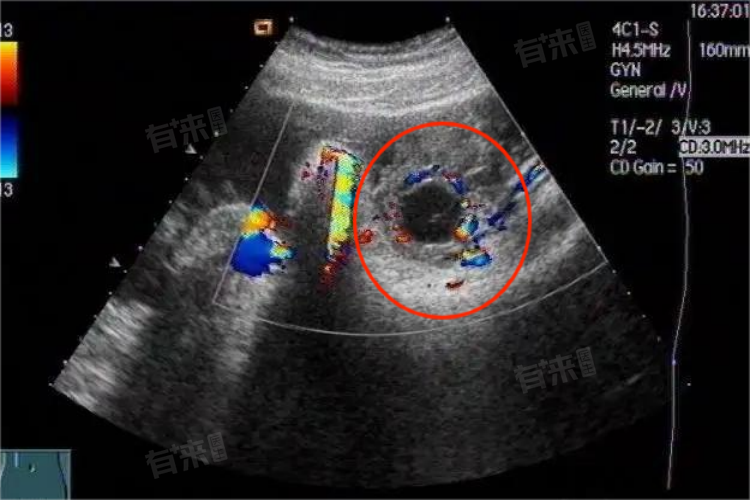

黄体囊肿破裂可由自发性、外力或医源性因素引起,治疗措施根据病情轻重包括一般治疗、药物治疗和手术治疗,及时正确处理对保障患者健康至关重要。